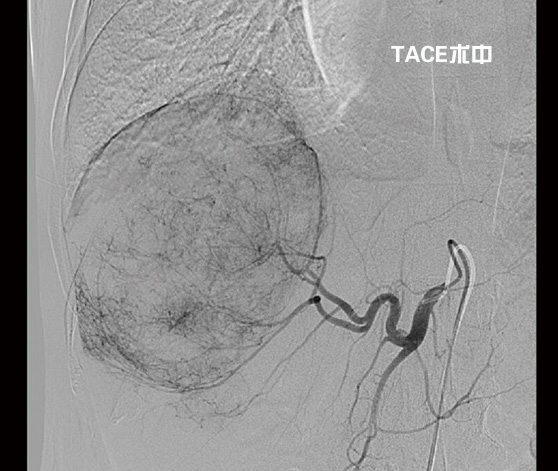

劉大爺在濰坊市市立醫(yī)院普外科接受了2次介入治療——經(jīng)皮經(jīng)股動脈穿刺肝動脈選擇性造影并肝癌灌注化療栓塞術(shù)(TACE)后,不僅巨大肝癌明顯縮小,而且又成功實施了肝第Ⅶ段、第Ⅵ段切除手術(shù)。日前康復(fù)出院時,劉大爺精神抖擻,滿面笑容,還調(diào)侃說癌癥再厲害也敵不過濰坊市市立醫(yī)院普外科專家的手術(shù)刀。

“這種情況不宜切除右半肝,因為左半肝體積小,余肝不能代償,切除后會導(dǎo)致肝功能衰竭,危及生命。必須先行介入治療,把供應(yīng)肝臟腫瘤的血管堵死, ‘餓死’癌細胞,使癌瘤縮小,左肝代償增大,待肝癌降期后再行手術(shù)治療,效果會比較好,也比較安全。”普外科首席專家李森主任分析說。期間劉大爺共經(jīng)過了2次介入治療,一個月前他來普外科復(fù)查時醫(yī)生告訴他腫瘤已明顯縮小,可以手術(shù),劉大爺心里一陣高興。